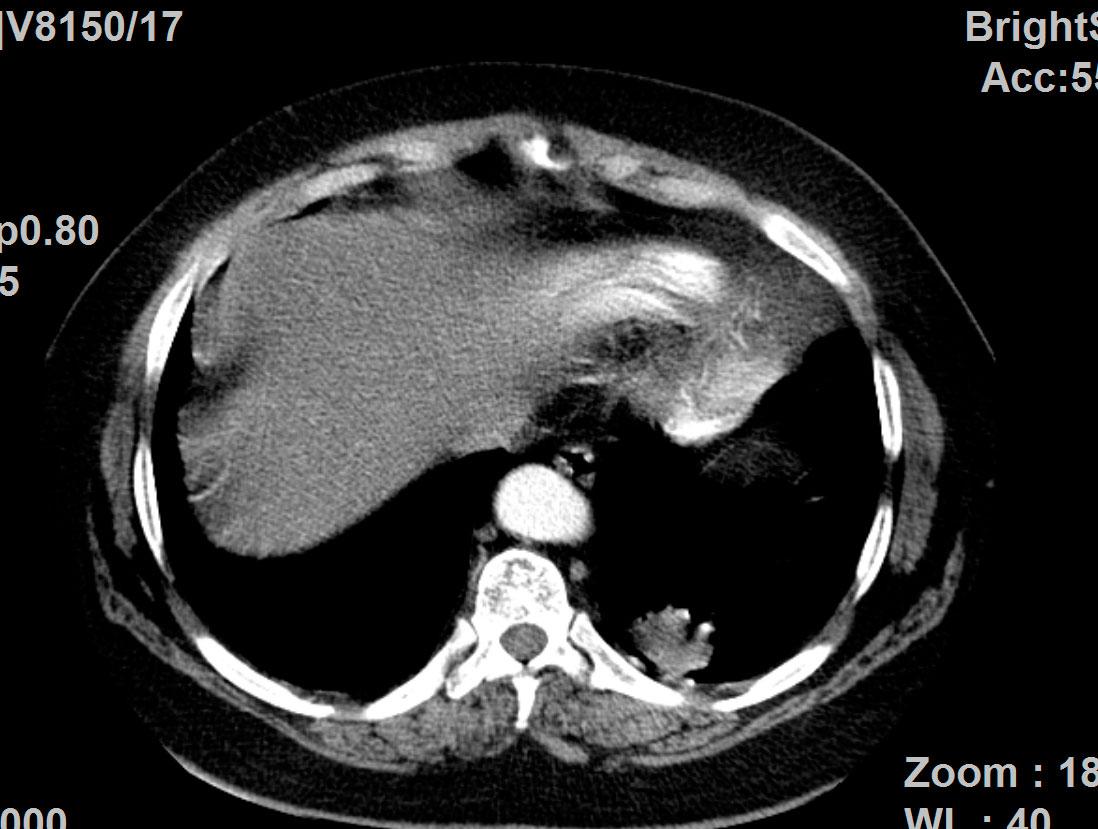

Lungenkrebs

Lungenkrebs befällt etwa 25 Prozent aller Krebskranken und gilt als häufigster Tumor beim Mann. Doch auch immer mehr Frauen sind betroffen. Die chirurgische Therapie ist für uns Mittel der Wahl, sofern keine Fernmetastasen vorhanden sind. Dabei können wir in unserer Klinik technisch hoch anspruchsvolle Lungenoperationen auf endoskopische Weise videoassistiert vorgenommen werden.

Technisch hoch anspruchsvolle Lungenoperationen können in unserer Klinik auf endoskopische Weise videoassistiert vorgenommen werden (VATS: Video-assistierte Thoraxchirurgie). Die bei konventionellen Lungenoperationen notwendige Eröffnung des Brustkorbs mit einem großen Schnitt und mit Auseinanderspreizen der Rippen entfällt bei der VATS-Lobektomie. Die Patienten erholen sich wegen der sehr viel geringeren Wunde („Operationstrauma“) sehr viel schneller. Auch sind die durch die Operation hervorgerufenen Schmerzen deutlich geringer. Bei einer anatomischen Operation mit Lungenteilentfernung müssen die „Versorgungsleitungen“ durchtrennt werden, dies sind die Blutgefäße und die Luftröhrenäste. Diese Operationsschritte und mehr können endoskopisch vorgenommen und über Video-Übertragung am Monitor mit Vergrößerung durchgeführt werden. Die Technik der VATS–Lobektomie/Lappen-Resektion wird bei Frühstadien des Lungenkrebses erfolgreich eingesetzt wie auch bei einer Vielzahl anderer anatomischer Lungenoperationen (Segmentresektionen).

Lungenmetastasen

Werden neben Lungenkrebs auch Lungenmetastasen diagnostiziert, stellt das die Medizin vor höchste Herausforderungen. Nur wenige Kliniken sind darauf spezialisiert, bei dieser Erkrankung chirurgisch einzugreifen. Durch besondere fachliche Expertise, einen großen Erfahrungsschatz und die technische Ausstattung ist unsere Klinik Ihr Ansprechpartner, wenn es um die chirurgische Therapie von Lungenmetastasen geht.

Laser-Chirurgie bei Lungenmetastasen

In unserer Klinik für Thoraxchirurgie werden zahlreiche Operationen an der Lunge mit dem modernen 1318NM-Diodenlaser durchgeführt. Das neue Gerät wurde speziell für die Lungenchirurgie entwickelt und hat besondere Eigenschaften, die das Schneiden von Lungengewebe ermöglichen: Mit dem Laser ist der Thoraxchirurg in der Lage, bluttrocken und übersichtlich durch das Lungengewebe zu schneiden. Dadurch können Metastasen und Tumoren, die tief im Lungengewebe liegen, onkologisch sicher entfernt werden. Anhand dieses modernen Verfahrens kann der Thoraxchirurg besonders gewebeschonend vorgehen und zahlreiche Lungenmetastasen entfernen, was mit konventionellen Methoden nicht möglich wäre. So kann die Prognose für den Patienten verbessert werden. Die sogenannte Laser-Metastasektomie ist eine etablierte chirurgische Behandlung, die bundesweit nur in großen Thoraxkliniken vorgenommen wird. Unsere Klinik ist die einzige in Ostwestfalen-Lippe, die Laser-Chirurgie bei Operationen der Lunge anbietet.